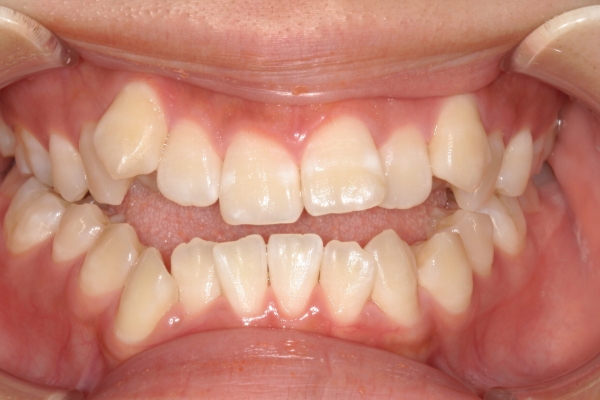

BEFORE

治療前

PROCESS

3か月

AFTER

治療後

骨格的に下あごが前下方に長いことが原因で、受け口、開咬(前歯が当たらない)の症状がでていました。また下あごが右にずれており、その影響で上下の歯列正中(真ん中)の大きなずれも生じていました。顎変形症手術も選択肢の一つでしたが、患者さまの希望もあり、下顎左側小臼歯の抜歯をして通常の歯列矯正で治療をしました。

前歯、奥歯の噛み合わせが大きく改善され、上下の歯真ん中が一致しました。食べ物が噛みやすくなったこともですが、歯列の見た目が整った点にも患者さまは満足されていました。